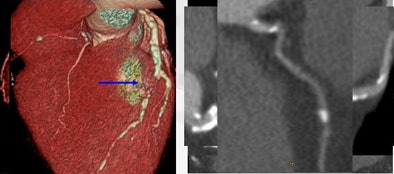

![]() |

| A diabetic patient with severe, diffuse artery disease encompassing three vessels was difficult to evaluate with 64-detector-row coronary CT angiography. There is occlusion in all segments of the left coronary artery, left circumflex artery, and right coronary artery. Image courtesy of Dr. Daniele Andreini. |